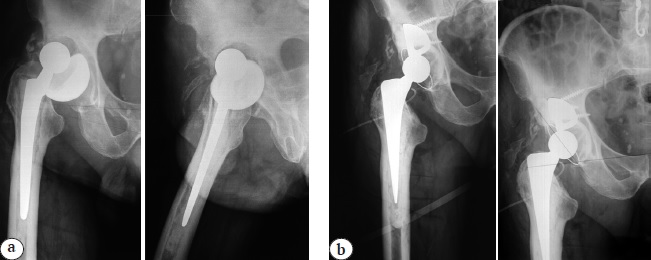

The patient experienced closed dislocation of the prosthesis later the day of discharge being at home in his sleep. He was admitted to the on-call hospital, where an unsuccessful attempt of closed reduction of the prosthesis led to the instability of the femoral component. One week later, the patient was readmitted to the department of septic osteology for surgical treatment. According to the patient, he had been taking the recommended ABT. X-ray showed total right hip replacement with unstable position of cemented prosthetic components with dislocation of the head of the femoral component (Fig. 2 a). No microbial growth was observed in the preoperative punctate.

Revision surgery with reinstallation of the acetabular and femoral components was performed 5 days after admission (27 days after one-stage revision arthroplasty). Double-mobility acetabular component and cemented (6.0 g meronem per 40 g standard package of DePuy CMW 3 cement (Johnson & Johnson, USA)) femoral component (Zimmer Biomet, USA) were implanted. Given the stable position of the augments, they were not replaced to prevent an increase of the bone defect.

Early postoperative period was uneventful. Control X-ray on the first day after the surgery showed right hip replacement with correct and stable position of the total prosthesis with cemented fixation of the components (Fig. 2b). On the 14th day after the surgery the patient was discharged from the hospital. At the outpatient stage, the patient was recommended to continue taking co-trimoxazole 0.96 g 2 times a day for 8 weeks.

Fig. 2. X-rays of the right hip on re-admission: a — on admission with signs of femoral component instability and prosthetic head dislocation; b — after repeated revision arthroplasty